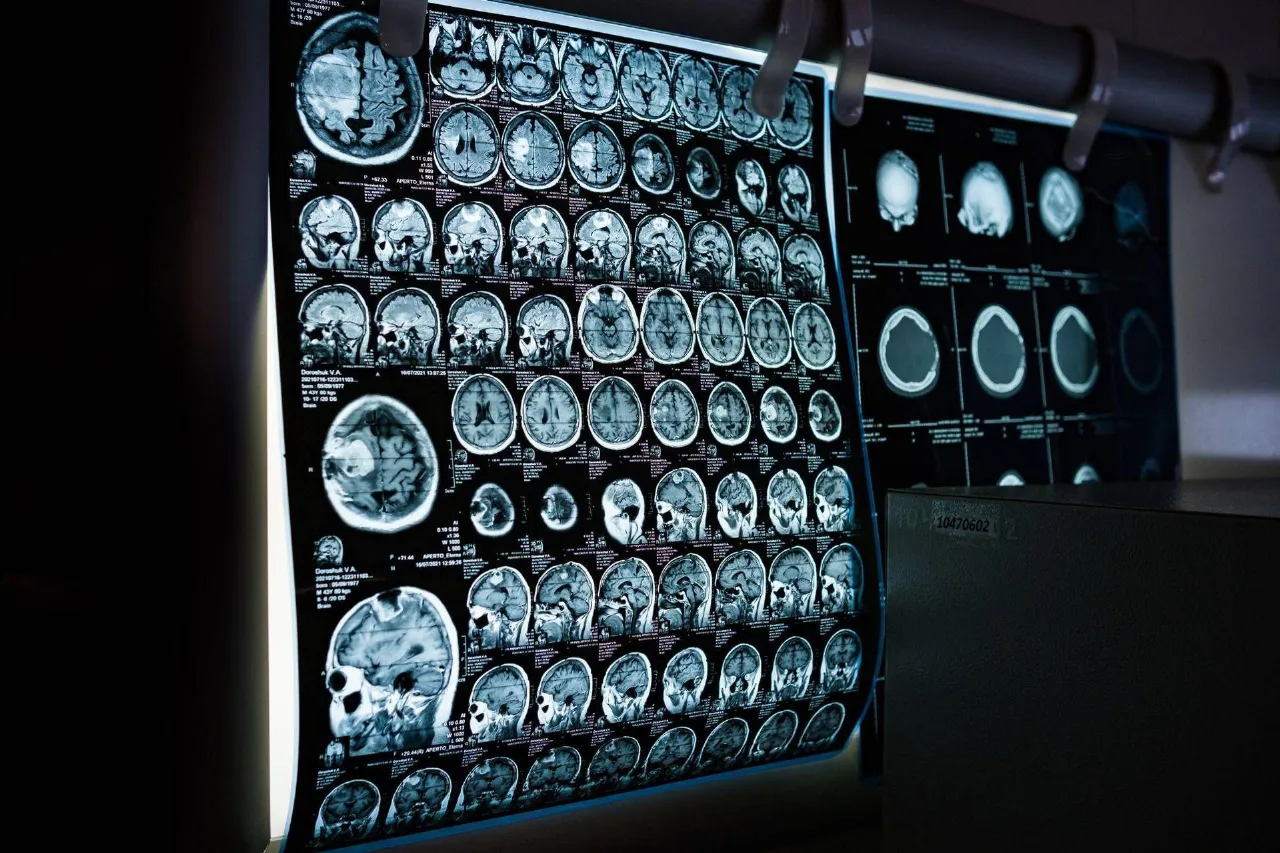

Un team della Texas A&M University ha sviluppato uno spray nasale capace di agire sui meccanismi dell’invecchiamento cerebrale. La ricerca, condotta negli Stati Uniti, mostra che il trattamento può ridurre l’infiammazione nel cervello e migliorare la memoria con poche somministrazioni.

Alla base della terapia ci sono minuscole particelle biologiche, chiamate vescicole extracellulari, che trasportano microRna. Queste molecole riescono a superare le difese naturali del cervello e raggiungere direttamente il tessuto nervoso, dove vengono assorbite dalle cellule immunitarie.

Una volta entrati in azione, i microRna intervengono sui processi legati alla neuroinfiammazione, spegnendo i meccanismi che alimentano lo stato infiammatorio tipico del cervello che invecchia. Questo fenomeno, associato a difficoltà cognitive e perdita di memoria, è considerato da tempo uno dei principali fattori di rischio per malattie come l’Alzheimer.

Guidato dal professore Ashok Shetty, il gruppo di ricerca ha osservato che il trattamento riesce a riattivare i mitocondri, le strutture cellulari che producono energia nei neuroni. Questo processo riduce lo stress ossidativo e restituisce efficienza alle cellule cerebrali.